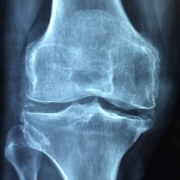

Musculoskeletal (MSK) health is crucial for everything we do, from walking and running to simply getting dressed in the morning. When something goes wrong with our muscles, bones, joints, tendons, or ligaments, it can significantly impact our quality of life. While exercise is a cornerstone of MSK recovery, physical therapy offers much more than just a workout routine. It provides a comprehensive approach to healing and regaining function, going beyond exercise to address the root causes of pain and dysfunction.